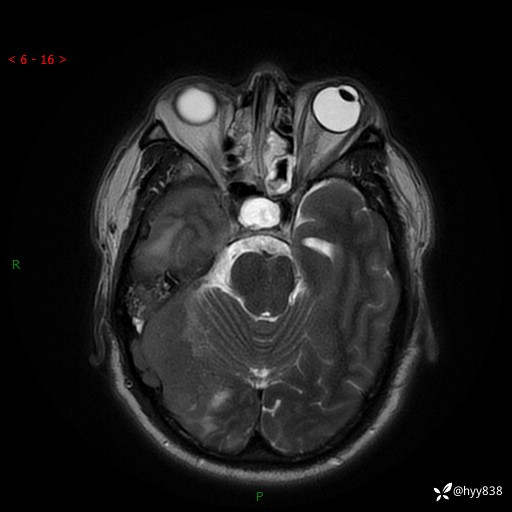

患者性别:男

患者年龄:56岁

简要病史:外院CT提示脑膜瘤,为进一步诊治来我院

辅助检查:MRI

临床诊断:颅脑占位

颅脑MRI平扫+增强